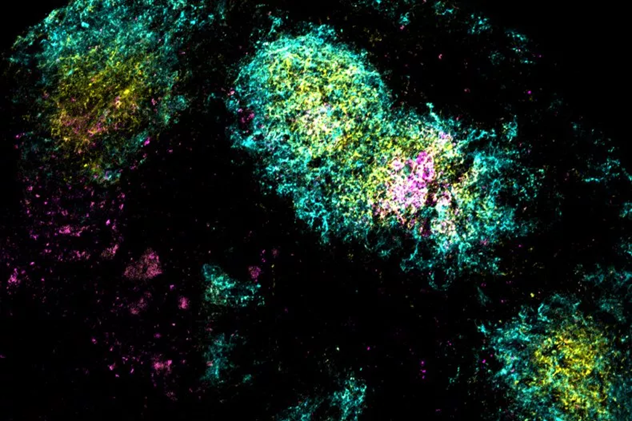

Hình ảnh kháng nguyên vắc xin (màu hồng) tích tụ bên trong nang tế bào B (màu lục lam) - Ảnh: MIT

Thí nghiệm trên chuột cho thấy, khi tiêm vắc xin bổ trợ kép, kháng nguyên HIV không bị phân hủy ngay lập tức mà tích tụ trong hạch bạch huyết lên đến 28 ngày. Hạch bạch huyết là “nhà máy” sản xuất tế bào B, nơi các tế bào này liên tục tiếp xúc với kháng nguyên để học hỏi và tinh chỉnh kháng thể. Nhờ đó, tế bào B có thêm thời gian để chọn lọc và tạo ra kháng thể có độ đặc hiệu và đa dạng cao hơn.

Các nhà nghiên cứu tách tế bào B từ hạch bạch huyết của chuột 14 và 28 ngày sau tiêm, rồi phân tích biểu hiện RNA để đánh giá mức độ đa dạng của tế bào. Kết quả cho thấy, so với nhóm chỉ dùng alum hoặc chỉ dùng SMNP, nhóm chuột nhận tá dược kép sản sinh gấp đôi số dòng tế bào B độc đáo, cũng như đa dạng hơn về kháng thể hướng đến nhiều vùng khác nhau trên protein HIV.